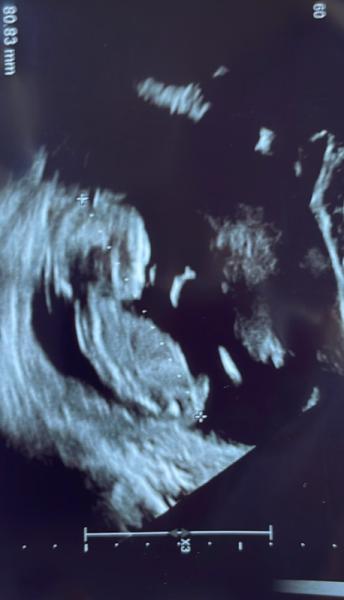

Hallo ihr Lieben, seit dem letzten Termin bin ich etwas verunsichert. Zum Einen wird die SSL im Verhältnis zur SSW immer größer. Bin bei dem Bild bei 12+5 und die SSL sind nun schon 8 cm, ist das nicht viel zu viel??? Außerdem mache ich mir Gedanken zur nackenfalte. Diese sieht so riesig aus, was sagt ihr dazu? Lieben Dank

Bei der Größe sagte sie selbst, hui das ist aber groß. Wobei mir etwas größer lieber ist als zu klein. Man sieht ja hinter dem Kopf einen weißen Strich, der mitten im Bild aufhört. Da habe ich sie gefragt, ob das die nackenfalte sei. Ist sie nicht weiter drauf eingegangen. Wenn ich mir so Bilder im Netz anschaue, sieht es demnach aus als wenn zwischen Kopf und Linie diese Flüssigkeit wäre

Man sieht ja hinter dem Kopf einen weißen Strich, der mitten im Bild aufhört. Da habe ich sie gefragt, ob das die nackenfalte sei. Ist sie nicht weiter drauf eingegangen. Wenn ich mir so Bilder im Netz anschaue oder auch das, was du angehängt hast, sieht es demnach aus als wenn zwischen Kopf und Linie diese Flüssigkeit wäre.

Das was du denkst sei die Nackenfalte ist die Eihaut, die Nackentransparenz sieht man in dem Bild nur ganz schwach und ist ganz schmal anliegend.